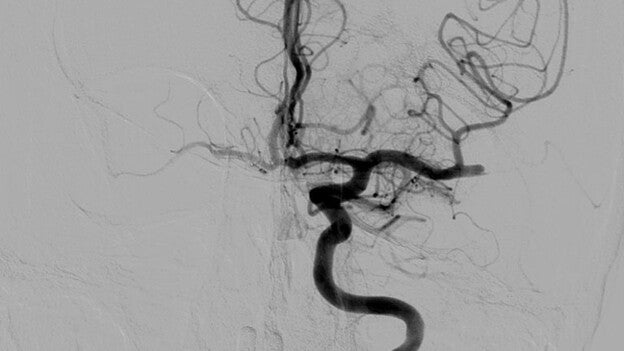

El consumo excesivo de alcohol altera el balance funcional en el cerebro, desconecta las regiones corticales mientras aumenta su acoplamiento con regiones subcorticales como el estriado, importantes para la motivación, recompensa y el establecimiento de hábitos de conducta.